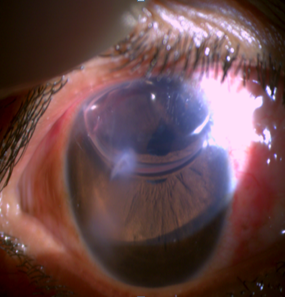

Before moving on the surgical procedure integrity of globe has to be restored then inflammation has to be subsided by systemic steroids and relevant medication. surgery was done under local anaesthesia, peribulbar block was given over massaging should be avoided as it aggravates zonular dialysis SMALL INCISION cataract extraction (SICS) with primary posterior chamber intraocular lens (PCIOL) implantation was done. In patient with corneal tear cataract removal with IOL implantation was done in two settings. In first setting corneal tear was repaired with 10-0 monofilament suture and in second setting cataract extraction with IOL implantation is done. In mild lenticular subluxation with partial zonulolysis SICS with PCIOL implantation was done depending upon the integrity of Posterior capsule. If posterior capsular bag integrity is good then a 1-piece PMMA IOL was implanted in bag.

If posterior capsule integrity is compromised and if enough of the anterior capsule remains to support and if proper anterior capsulorhexsis was possible then a 3-piece PMMA IOL implantation was placed in ciliary sulcus. If posterior capsule was severely compromised and more than half zonulolysis then secondary IOL placement preferably iris claw lens was done. In few cases where cataract was densely attached to posterior capsule, posterior capsulotomy was done and IOL was placed in the bag. Data was analysed with regard to relationship between different causes of trauma and, resulting injury and final visual outcome achieved with surgical technique. Patients were subsequently followed up at 1 week, 1 and 6 month and best corrected visual acuity was recorded.

In our study we found that corneal involvement was most common associated ocular damage ([Figure 6], [Figure 7]) and it was found that it is one the most common cause of reduced visual acuity following penetrating trauma.

Associated ocular injuries (Fig. 1-4)

Before and after surgery (Fig. 5-8)

Our study concludes that the younger males common sufferer than female due their more involvement in outdoor activities. Penetrating injuries being more frequent than the blunt injury. Blunt injury has better visual outcome than penetrating injury because structural integrity is maintained. In case Penetrating trauma BCVA is less due to associated ocular injury, more of corneal involvement. It also depend various factor ranging from force of trauma affecting anterior and posterior segment ([Figure 6], [Figure 8]), severity of damage, any preceding ocular conditions, proper and timely medical and surgical management of these cases, and management of post operative complications and regular followup.